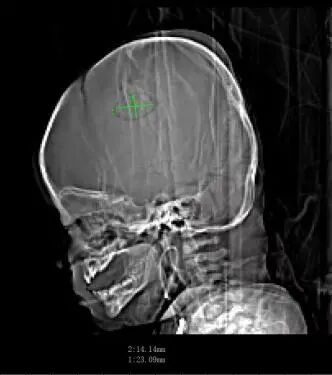

手術(shù)機(jī)器人、神經(jīng)導(dǎo)航精準(zhǔn)定位